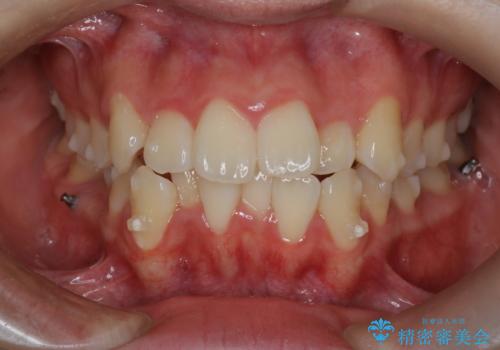

【インビザライン】前歯の凸凹を非抜歯で治療

- 前歯の凸凹を主訴の来院されました。

奥歯を後ろの方に移動させるために矯正用のアンカースクリューを使いながら治療をおこないました。

患者さんの都合により、マウスピースの装着時間が不足したため、途中からワイヤーにて治療を行いました。

インビザラインは20時間以上の装着は必要となるため、患者さんによってはワイヤーの方が向いていることがあります。